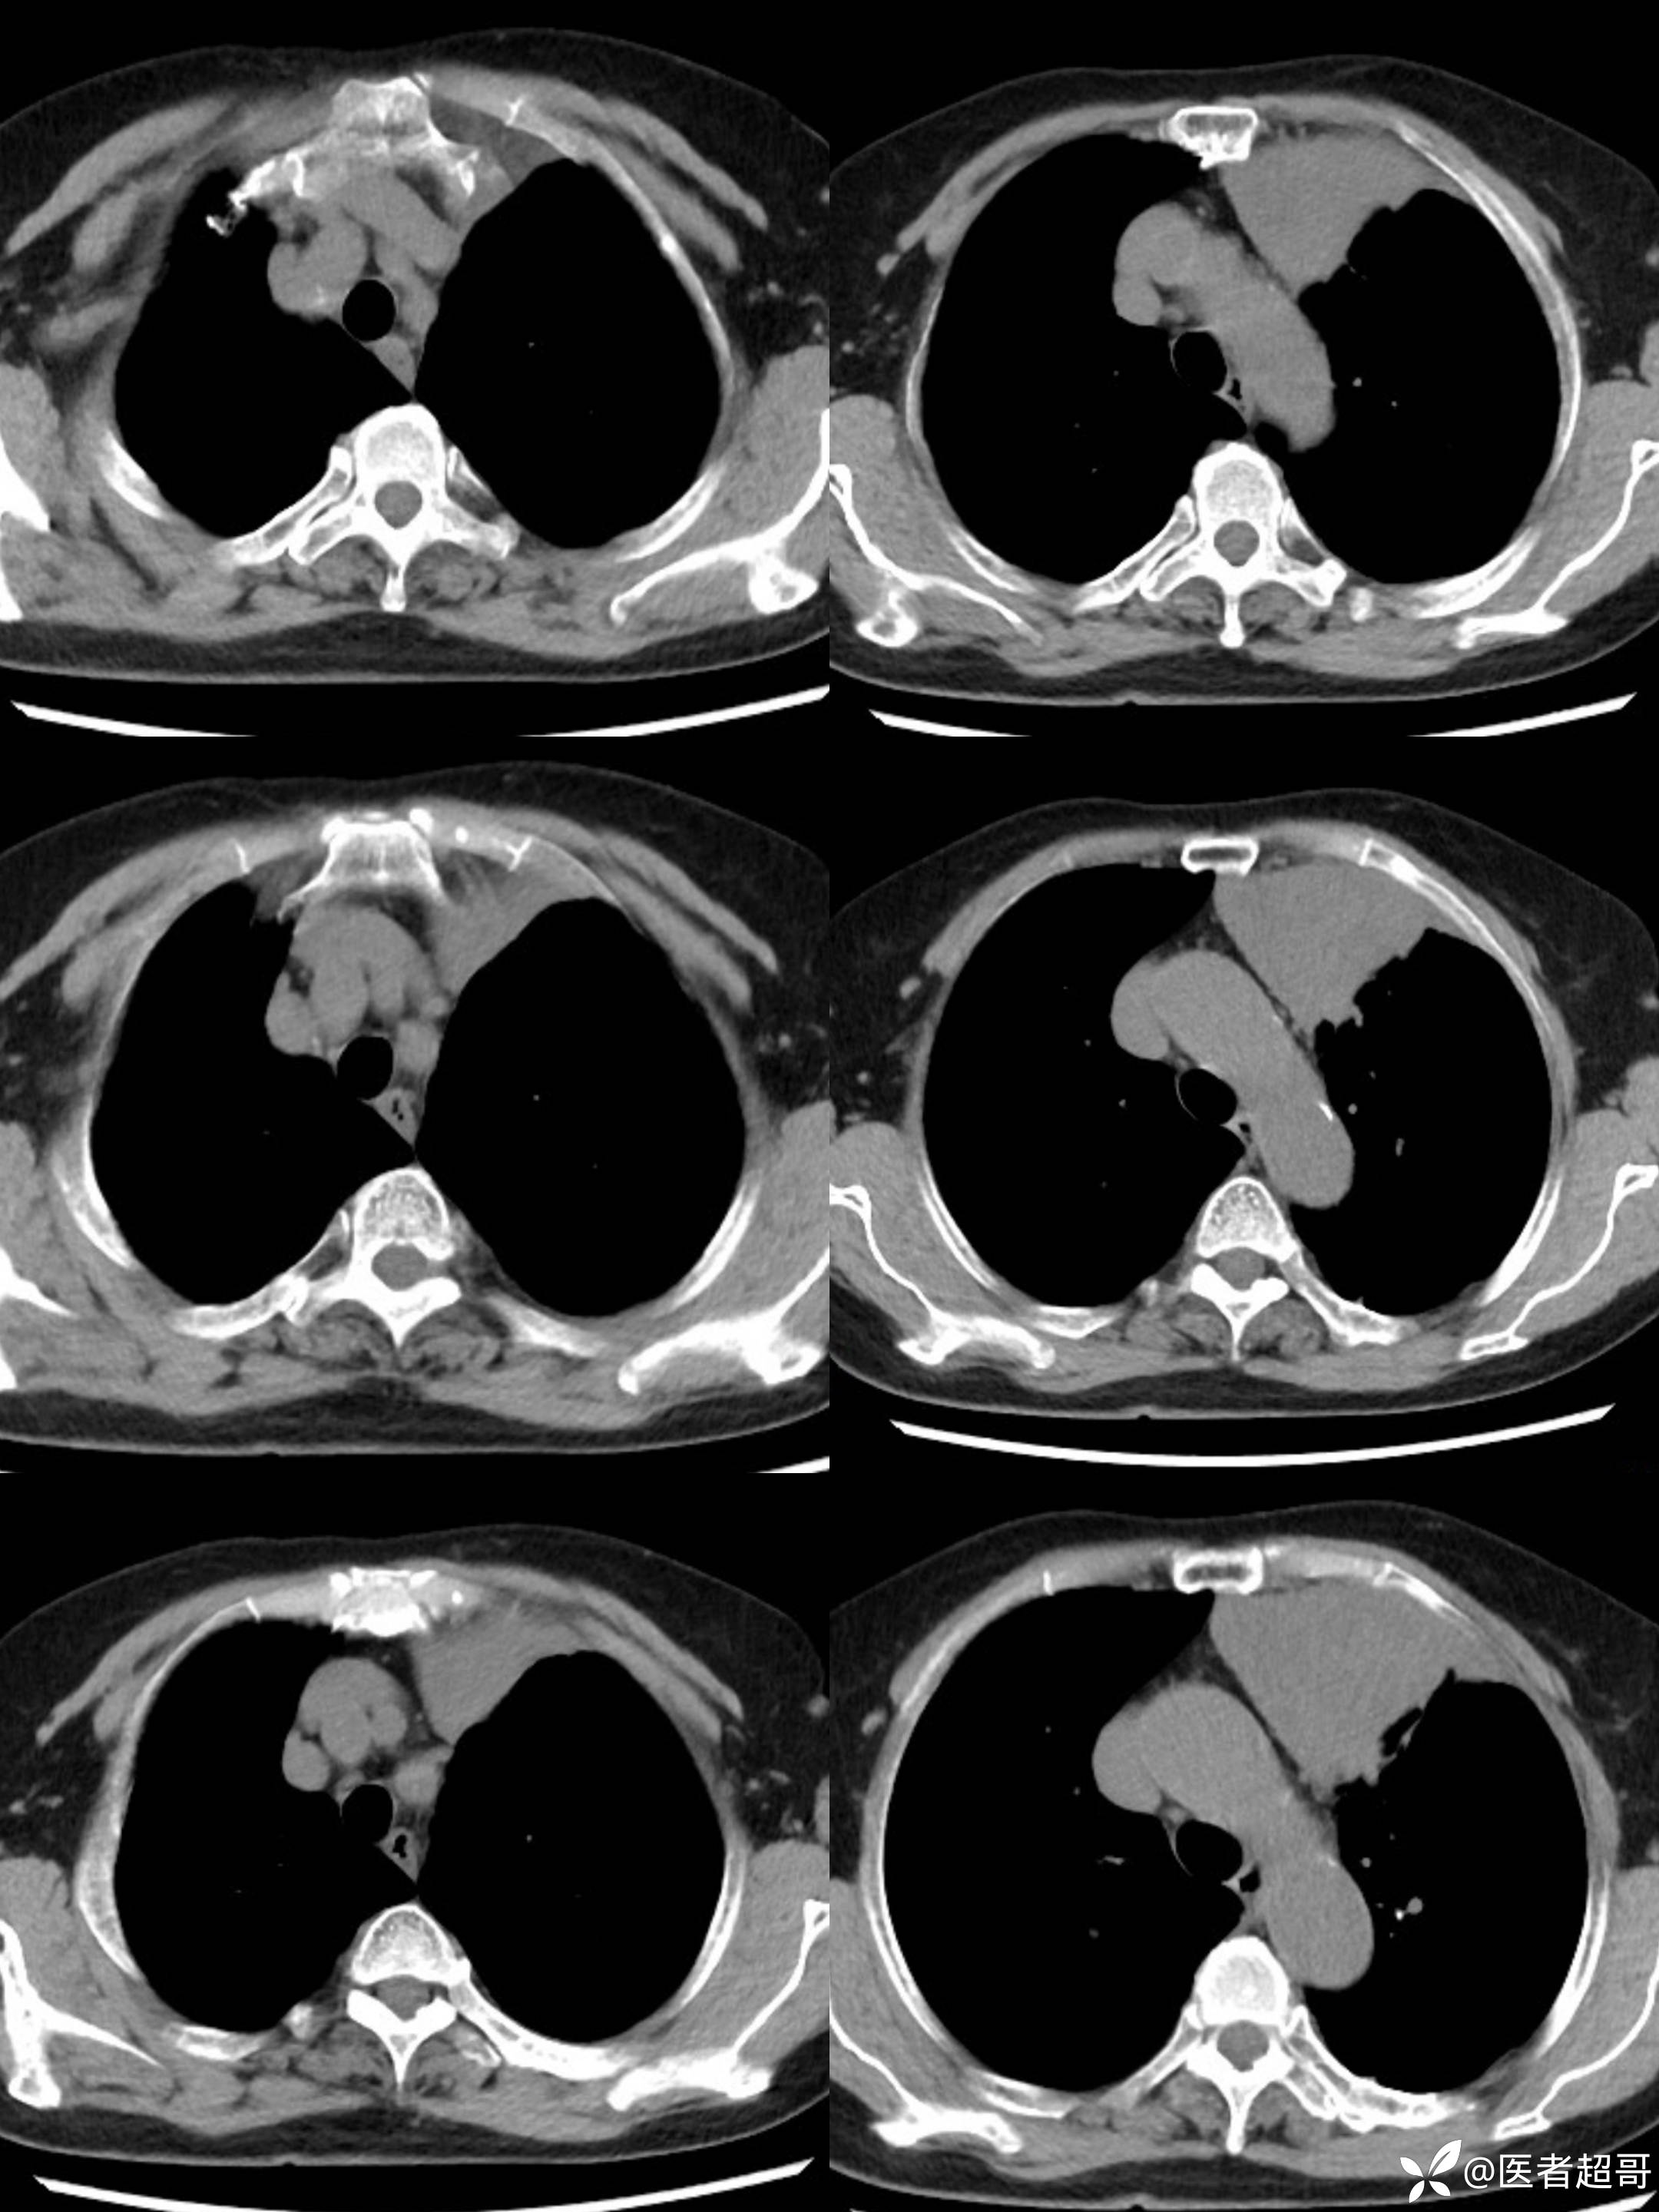

女73岁,体检发现左上纵隔占位1周

患者于1周前体检行CT检查提示:“左上纵隔见不规则团块状软组织密度影,大小约90*63mm”,患者平素偶有头晕,无明显胸闷气急,今为进一步治疗来我院就诊, 门诊以"左上纵隔肿物"收入院。

糖类抗原125(CA125):44.9(正常0-30.2),余实验室检查无殊